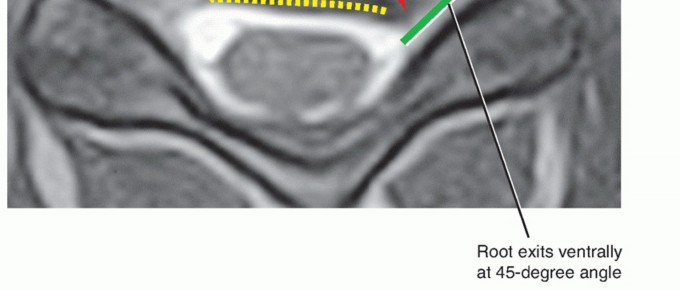

### TECH FIG 1 • A. The discectomy should be performed from uncus to uncus. The upslope of the uncinate is clearly defined with curettes and Kerrison rongeurs until these borders are unquestionably identified. Having a wide discectomy allows for placement of larger grafts or supplemental grafts in the uncinate regions. B. ACDF graft carpentry in a patient with three level cervical spondylotic myelopathy. Creating parallel disc spaces facilitates graft-host bone contact, securing an intimate fit as well as allowing for wide decompression of spurs arising from the posterior disc space. Posterior spurs along the floor of the canal have been removed at each level, decompressing the spinal cord. The central portion of each endplate is maintained as much as possible to optimize structural integrity. At C6-C7, two grafts have been inserted in order to fill the disc space as much as possible (note as a result the different appearance of the grafts at C6-C7 vs. the proximal levels). ### Use of Distraction: Pins, Tongs, and Spreaders Intervertebral body distraction pins can be placed to gently distract the disc space and improve visualization. Generally, this is done after an initial superficial discectomy, which allows greater disc space mobilization with the pins. Because greater preparation of the inferior endplate of the superior vertebra is usually needed, the Caspar pin should be placed more cephalad in the cephalad vertebral body (TECH FIG 2). Overdistraction of the disc space is not desired. If the disc space is fused in an overdistracted position, postoperative neck pain may result. If there is a significant compressive lesion on the spinal cord, distraction should be avoided until the compression has been relieved to prevent stretching or tenting of the cord over that lesion. An additional benefit of the Caspar pins is that they help to retract the soft tissues in a cephalocaudal direction without the use of a secondary set of retractor blades. Alternatively, a small laminar spreader can be used in the contralateral disc space instead of Caspar pins to provide distraction. ### Endplate Preparation The inferior endplate of the cephalad level is concave, whereas the superior endplate of the inferior level tends to be relatively flatter. Thus, to achieve intimate contact of bone graft with both 4 endplates, a rectangular space is created by parallel decortication of the endplates.

### TECH FIG 2 • Caspar pin placement. Because greater preparation of the inferior endplate on the cephalad vertebra is necessary, the surgeon should place the upper Caspar pin (C5) further away from the endplate (eg, in the midbody of C5 or more cephalad) while being cognizant of not entering the adjacent disc space above. The Caspar pins are placed in the midline to avoid compromising later screw fixation during plating. To achieve parallel distraction, the pins should be placed parallel to the disc space. If the tips (ie, the leading ends) converge, relative kyphosis of the disc space occurs with placement of the Caspar pin spreader and distraction; if the tips diverge, relative segmental lordosis occurs with placement of the Caspar pin spreader and distraction. It may be desirable at times to try to increase lordosis through this mechanism. This generally requires greater preparation of the inferior endplate of the cephalad level versus the superior endplate of the inferior level. It is important not to remove too much bone off the inferior endplate of the cephalad level, however, as doing so limits the bone available in the vertebra to accommodate a plate and screws. This is particularly the case in smaller patients who have smaller vertebrae. A high-speed burr is helpful in decorticating the endplates. The creation of a parallel rectangular space within the disc space allows insertion of a graft appropriately sized to match the larger height present at the center of the disc space. Both endplates should be thoroughly denuded of cartilage and decorticated to reveal bleeding bony surfaces to enhance the chance of successful fusion.5 Alternating use of the high-speed burr, curettes, and the pituitary rongeur will allow the surgeon to reach the posterior disc space and the PLL. During ACDF, we are more aggressive with endplate preparation than during corpectomy because ACDF grafts tend to be more stable than corpectomy grafts. If major endplate resection is performed during corpectomy, significant settling or pistoning of the graft may occur (see Chap. SP-7), which is less likely with ACDFs. Furthermore, in cases of extensive spondylosis, wide disc space preparation facilitates decompression along the floor of the canal in ACDF surgery. When performing corpectomy, on the other hand, the additional room is not usually necessary because removing the vertebral body creates wide access for work at the disc level. ### Anterior Foraminotomy The discectomy is performed to the level of the PLL, with complete removal of the posterior annulus. It is safer to leave the PLL intact during the initial foraminotomy or resection of posterior osteophytes when the burr is being used because it acts as a protective layer to the neural elements. Once the bony removal is complete, the PLL can then be resected.2 The medial half of the posterior uncinate is thinned under direct visualization with a high-speed burr to unroof the entry zone of the foramen (TECH FIG 3). The microscope is angled appropriately to visualize the uncinate. In general, it is easier to decompress the contralateral rather than the ipsilateral foramen, although decompression of both is certainly possible. Thus, in cases of unilateral radiculopathy, we prefer to approach the spine from the side opposite to the patient's symptoms. It is important not to force a large instrument into a severely narrowed foramen if it does not fit easily. Instead, the surgeon 5 should use the burr to thin the uncus until the instrument can easily be passed into the foramen.